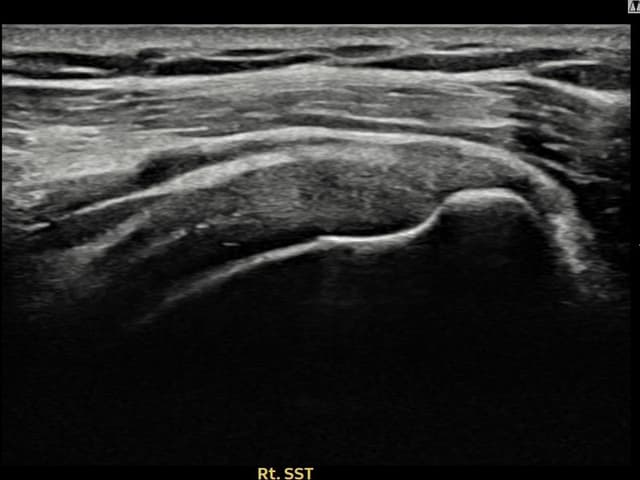

[촬영시기:21.11.15~21.12.02]

[석회분쇄흡입술] 우측 어깨 극심한 야간 통증으로 수면을 이루기 어려웠던 50대 여성 환자로, X-ray에서 극상근건 내 다량의 석회 침착이 확인되어 석회분쇄흡입술을 시행하였습니다.